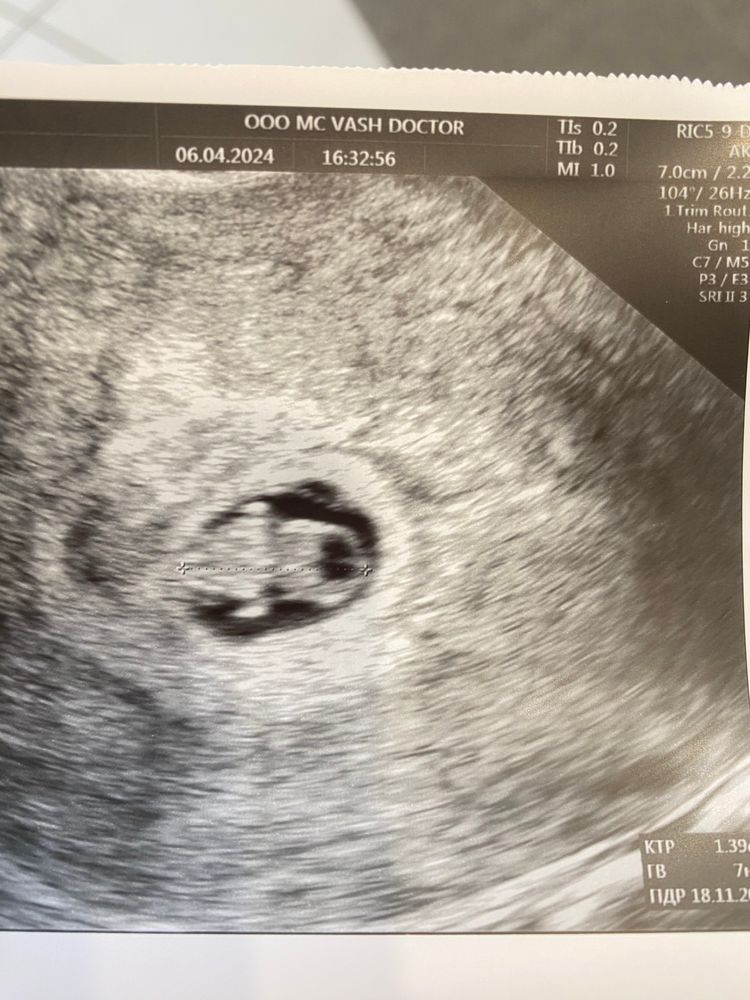

Осмотр в беременность, вопросыДевочки, миленькие поделитесь своими историями. По КТР малыш на 7н5дн, а плодное яйцо на 6 недель. Малыш хорошо развивается, с сердцебиением, а вот плодное яйцо от него отличается на 2 недели практически. Хороший исход в итоге был? Первый раз с этим сталкиваюсь если честно

Anna Fort, неделю назад было на 5 недель, сейчас на 6, в принципе развивается, но не так резво, как сам эмбрион